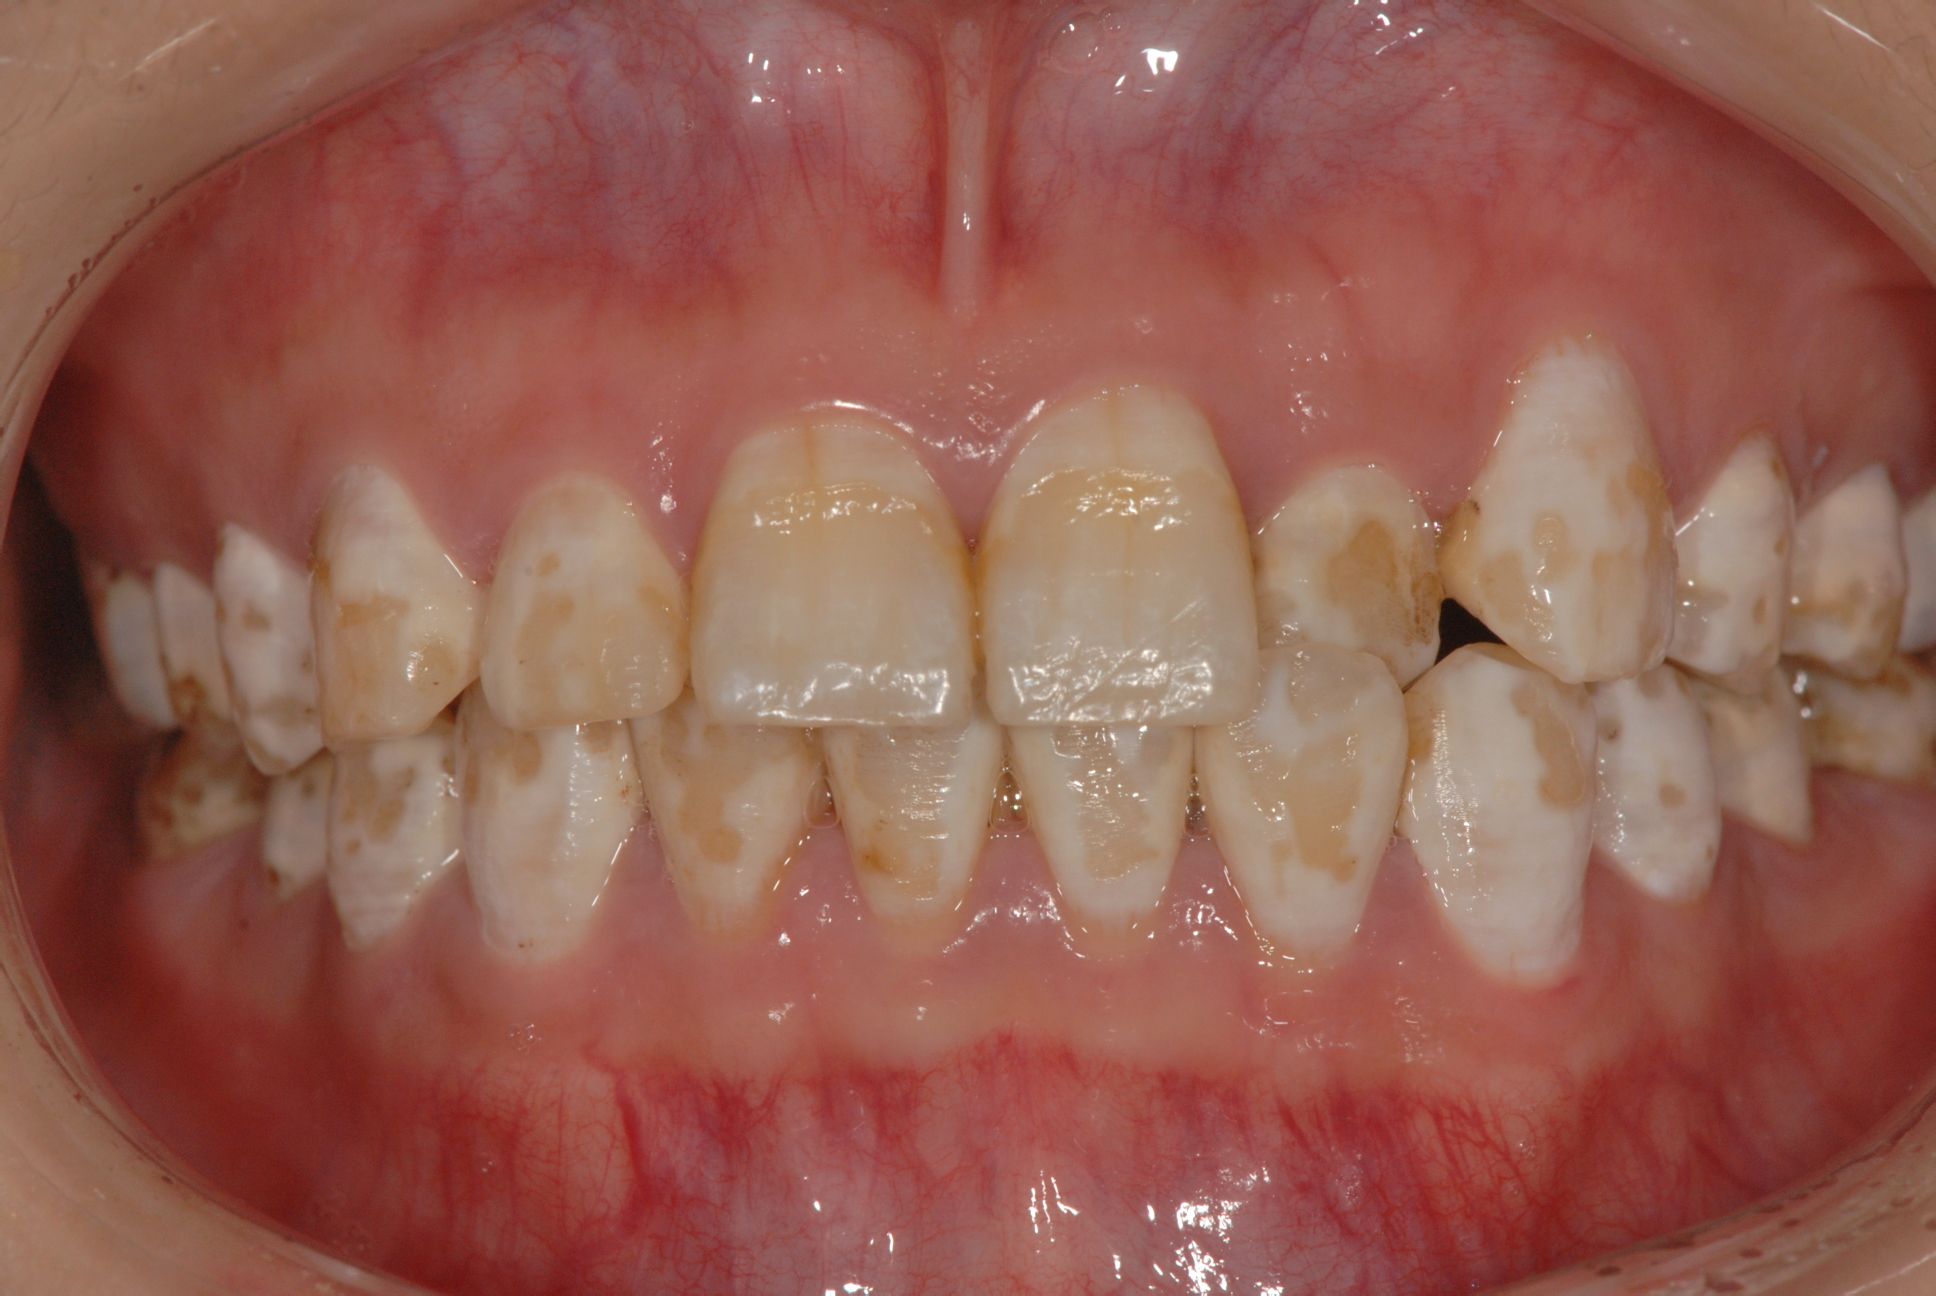

氟斑牙是慢性地方性氟中毒较敏感而突出的症状,其临床表现主要为白垩、着色、缺损。氟斑牙的棕黄色着色和不规则的釉质缺损不但影响美观,而且对患者造成了心理上的负担,因此,有效地去除氟斑牙表面着色,改善牙齿的外观,同时又要尽可能地保存牙体组织是氟斑牙治疗方面急需解决的问题。